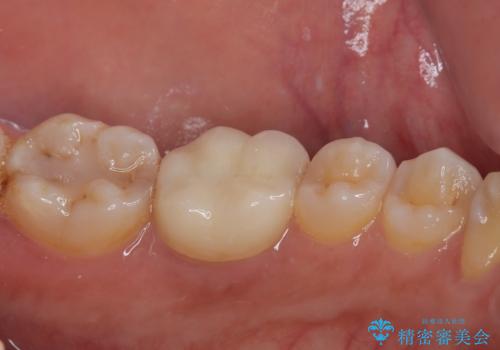

機能面、見た目共に満足していただきました。今後はメンテナンスで通っていただく予定です。